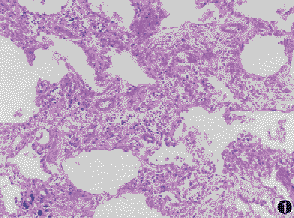

NSIP的組織學特徵包括不同程度的間質炎症和纖維化,具有一致性的外觀。富細胞型NSIP顯示輕度到中度的間質慢性炎症浸潤,基本沒有纖維化;纖維化型NSIP顯示間質增厚,為新舊一致的纖維化,肺泡結構完整,伴不同程度的細胞炎症。

非特異性間質性肺炎的分析NSIP在病理學上主要需與UIP相鑑別。NSIP的特點為:肺泡壁明顯增厚,含有不同程度的炎症與纖維化表現。病灶可呈片狀分布,但最重要的特徵是在病變時相上的一致性,即不同部位的病變似乎都是由發生在一個狹窄的時間段內的損傷引起的,並且共處於炎症纖維化進程中的某一階段,在同一標本上見不到象UIP那樣的新老病灶共存的現象。然而在不同病例之間,炎症與纖維化的程度和比例可能有很大差異,並可據此將病人分為3組。第1組只有細胞性炎症而幾乎沒有纖維化,第2組炎症與纖維化並存,第3組有緻密的間質膠原沉積,只有輕度炎症並缺乏活動性纖維化表現。3組約各占50%、40%和10%。總的來說NSIP對肺泡結構的破壞較輕,即使是第3組病人也極少見到蜂窩樣改變。有的病人可有BOOP樣改變,但根據定義,NSIP標本中的BOOP樣病灶應占總體病變的10%以下。